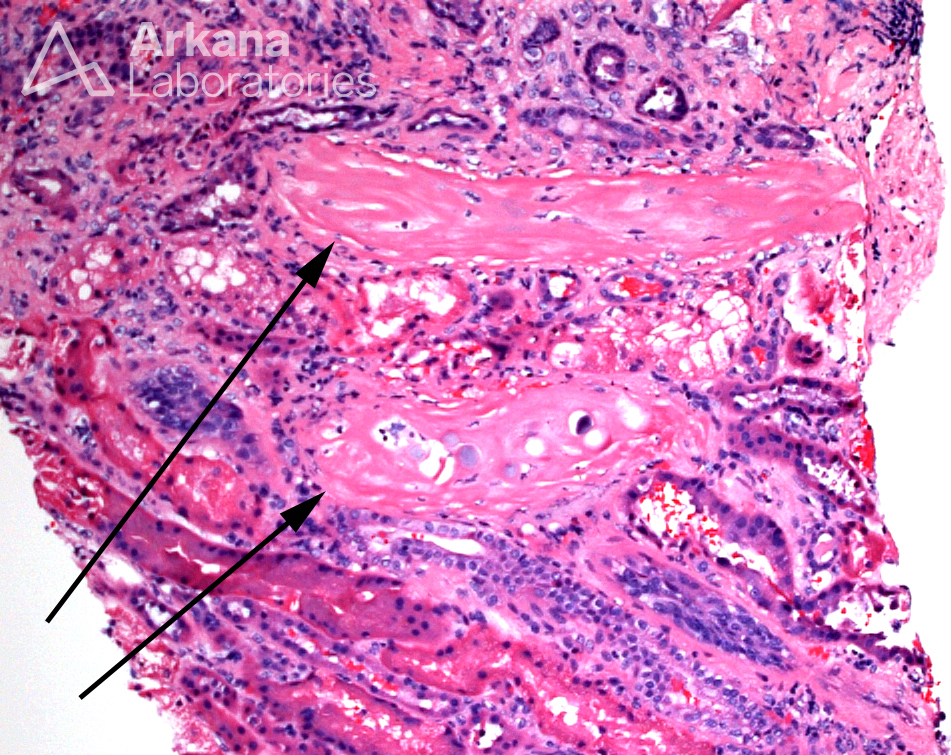

Today’s teaching point is a true “zebra” in renal pathology. The arrows in the light microscopic image identify what have been called renal sclerosing peritubular nodules, which are foci of peritubular spindle cells with myofibroblastic differentiation and variable amounts of